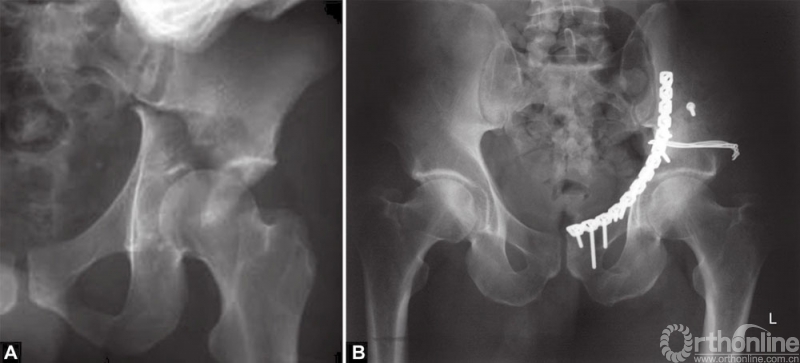

A和B从后向前进行复位,放置骶髂关节钢板进行固定,通过前入路放置长的后柱螺钉